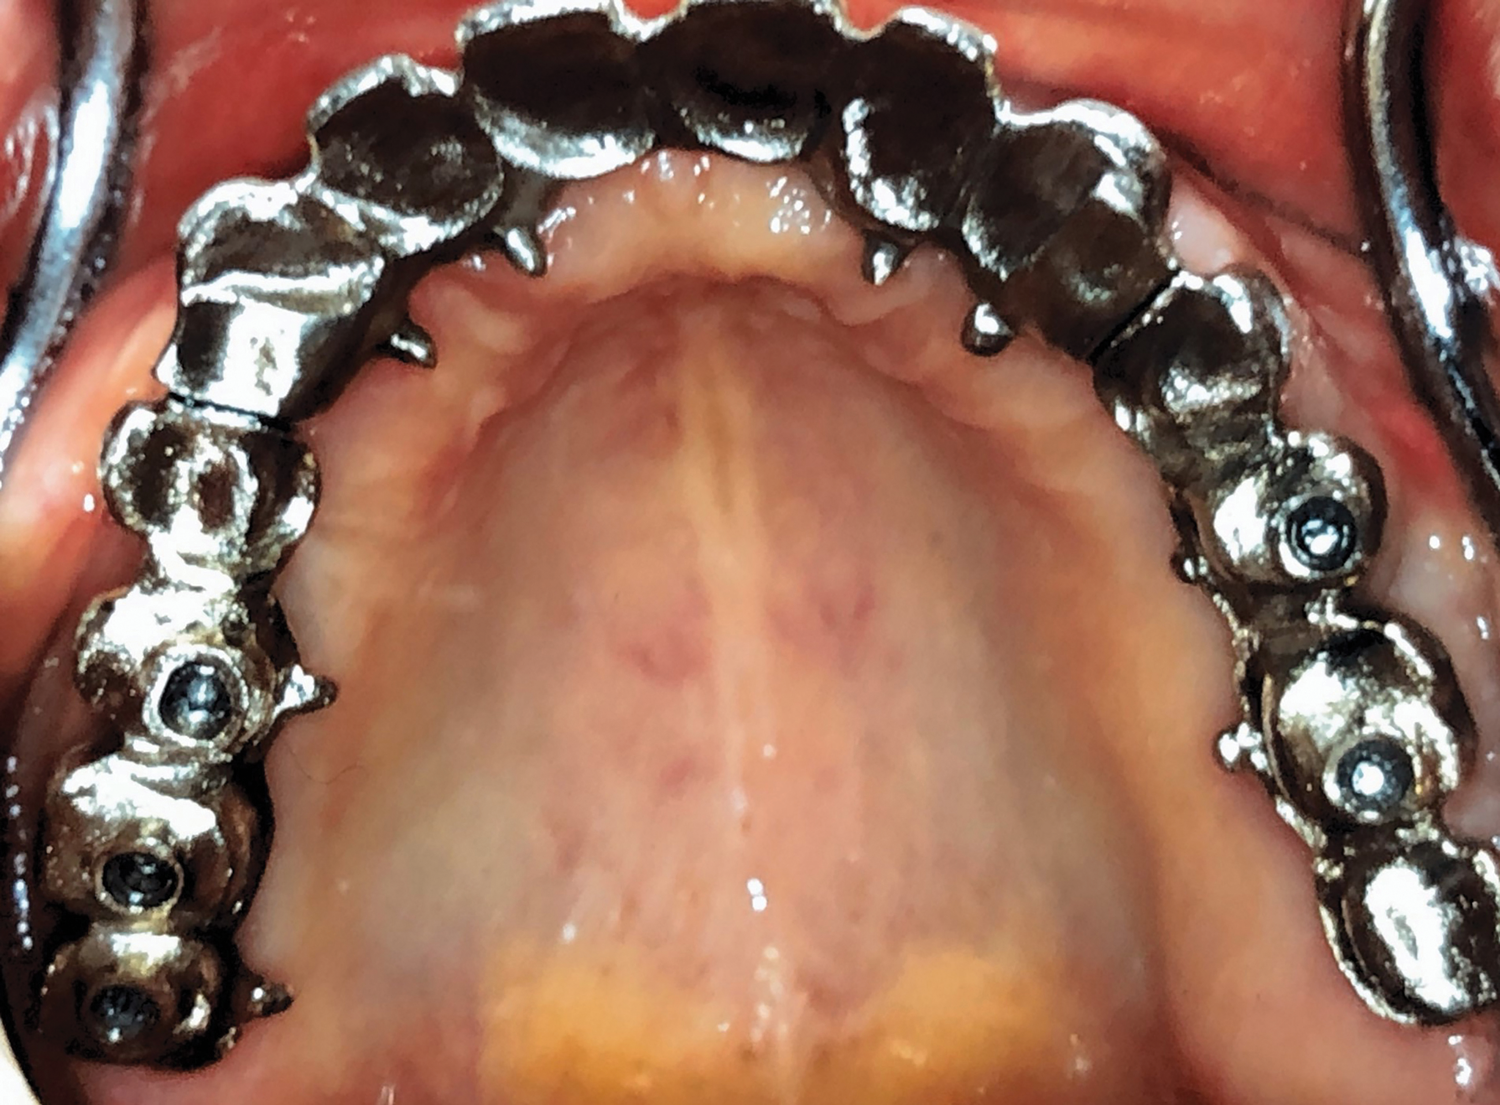

Fig 14. Maxillary arch with metal framework.

Figure 14

A final impression was made (Figure 13). Interocclusal registration also was taken, and a facebow was recorded. A buccal matrix and teeth set-up were fabricated to evaluate the available space for the final prosthesis, as well as occlusion, esthetics, and phonetics. Custom abutments were screwed in on implants Nos. 6, 8, 10, and 11, and octa abutments were screwed in on implants Nos. 2, 3, 4, 13, and 14. The fit was verified by periapical radiographs. Metal frames (one anterior section and two posterior sections) were tried-in for passive fit, a bite registration was recorded, and a pick-up impression was performed. Two interlocks, one in each extremity of the anterior segment, were included (Figure 14).